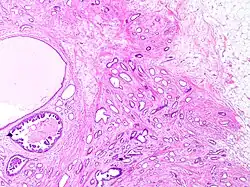

Histopathology of tubular carcinoma, high magnification, H&E stain. It shows the typical features of tubules lined by a single layer of cuboidal to columnar epithelial cells with small to intermediate sized nuclei low grade nuclei and sparse mitoses (grade 1).[1]